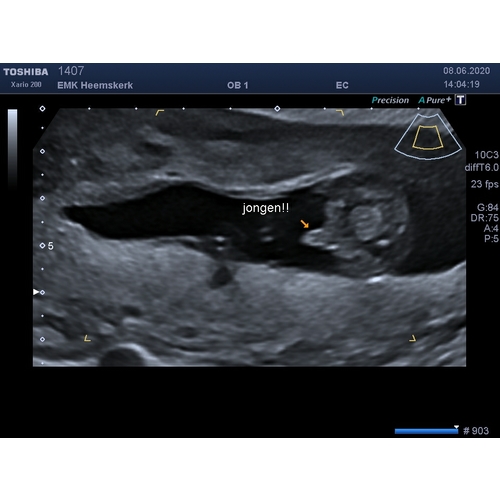

Ze bedoelt het zoontje waarvan ze zwanger is🙈 haar 11 jarige zoon is een s ...